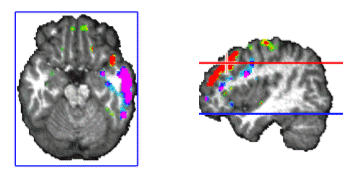

One interesting finding of this analysis was that we often observe strong activity localized at brain voxels located at near the putative position of the thalamus in our head model. Such deep activity corresponded even with the maximum or the minimum at some punctual times that preceded the spindles. Such strong thalamic activity was never observed at the spindle during the times of maximal spindle waning or waxing. Later observation reveals that deep brain activity can be observed at the scalp and thus localized with inverse solutions when the cortical areas are relatively silent and the deep activity is strong. This is likely to be the case for sleep spindles for which thalamus is known to be a basic generator. One example of such activation is presented in Figure 9.

Magnify

Figure 9. Voxels at the putative localization of the thalamus can appear as the maxima or the minima of the activity recovered by ELECTRA inverse solution. Here the maximum is indicated by the red cross. Thalamic activity was often observed preceding the start of the spindle, i.e. when cortical areas were practically silent.

Figure 10. Stable temporal lobe activity is observed during the inter-spindles intervals.

We were also interested in analyzing the stability and generators of the activity during the inter-spindles intervals. Experimental evidence (Sirota, et al. 2003) indicates that sleep spindles promote hipoccampas ripples after a certain temporal delay. It is therefore interesting to explore the areas activated after spindles. We did in fact found stable activity after all spindles explored. The stability occurred preferentially after the slower 12 Hz spindles that showed maxima at temporal brain areas. In general the frontal maximum observed during the spindle shifted toward temporal areas of the same hemisphere where the frontal maximum was found. This effect is illustrated in Figure 10. The sequence of maps show the end of the spindle with the right frontal maximum and minimum followed by the increase in activation at the right middle temporal lobe that soon becomes the maximum. Activity is progressively shifted towards the right superior temporal gyrus. The axial slide shown in Figure 11, at the level of the blue line shown in the rightmost inset, illustrates that the temporal activity observed after spindles is not restricted to the cortex but also involves deep temporal lobe structures such as the hippocampal/amygdala formation.

Figure 11. Simultaneous cortical and subcortical activity (amygdala/hippocampus formation) is observed during the interspindles interval.